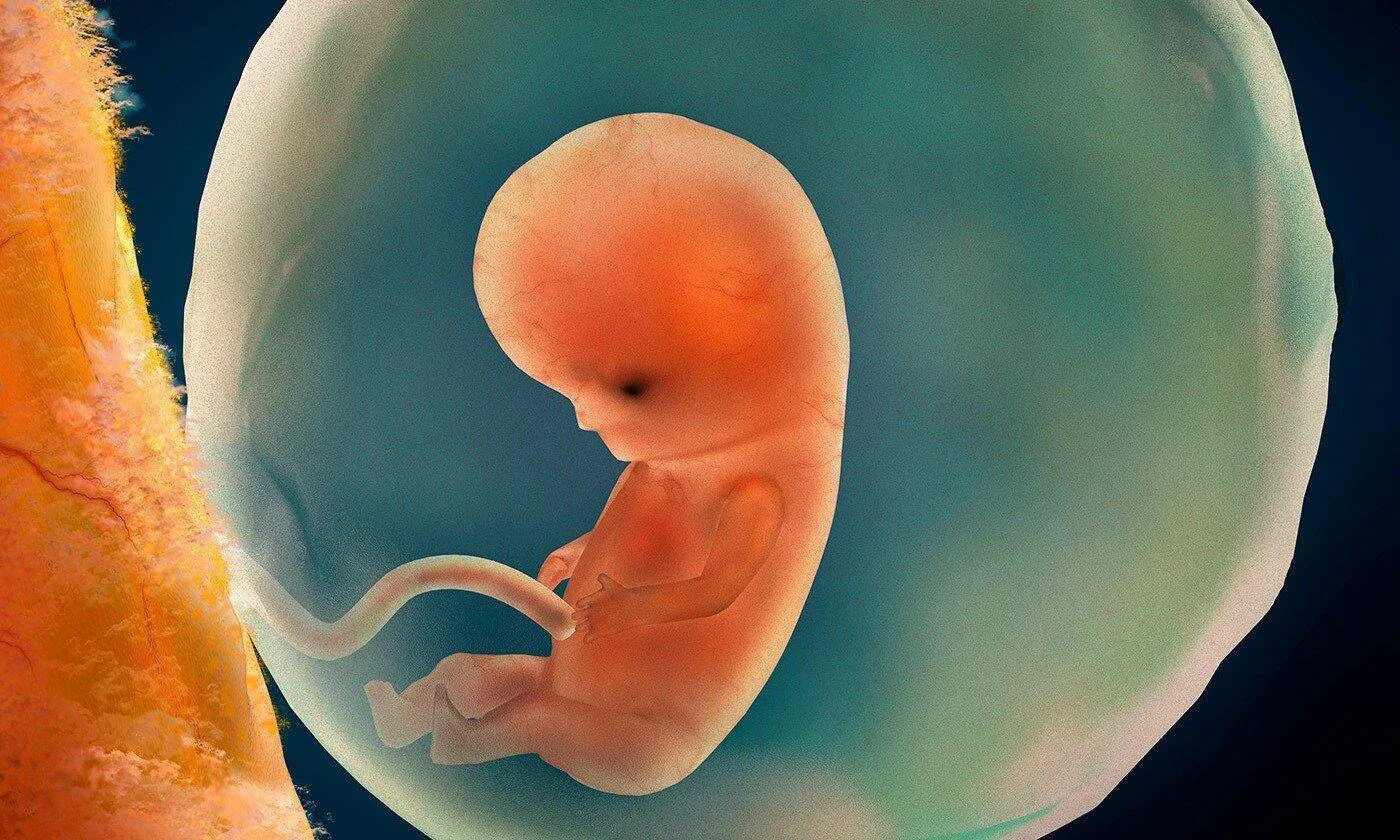

9 5 неделя беременности